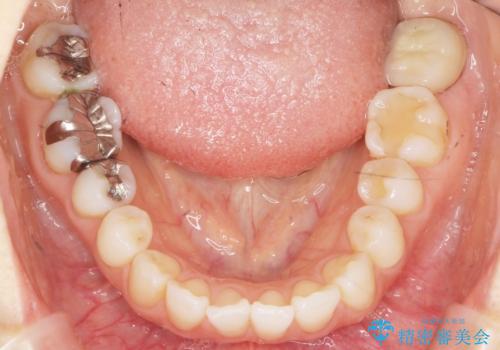

歯が割れた 親知らずの移植 30代女性

- 昔何回か根管治療した奥歯が膿んでいていて痛みがあることを主訴に来院された患者様です。

精査したところ、左下の奥歯にはひびが入っていて、保存不可能な状態でした。

義歯・インプラント・親知らずの移植の選択肢を提案したところ、移植をご希望されました。

割れている奥歯を抜去後左上の機能していない親知らずを移植し、生着したのち根管治療・補綴を行いました。